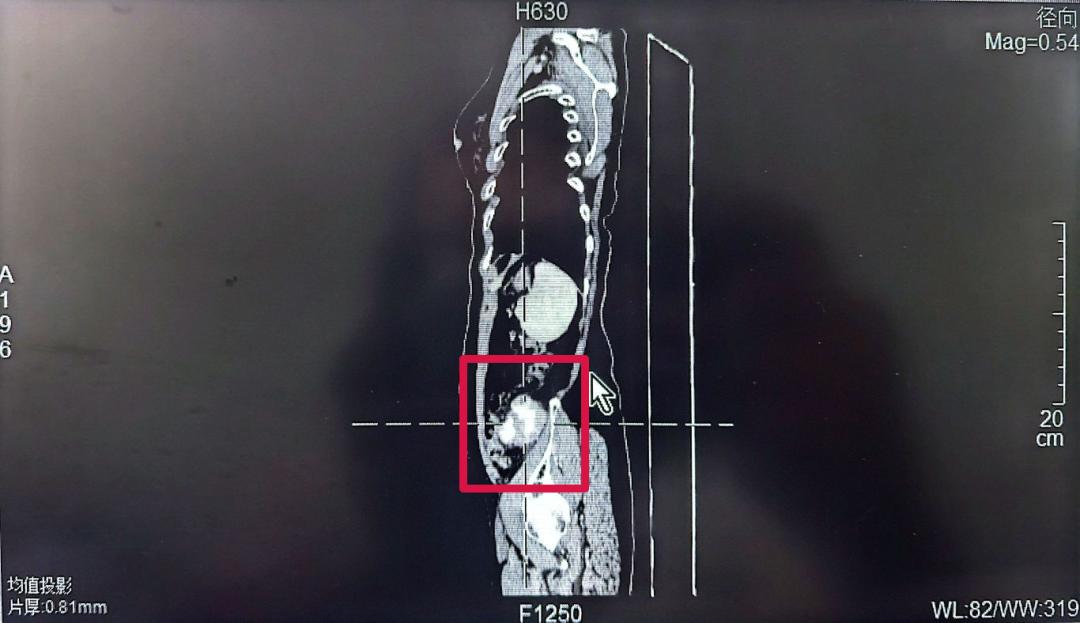

69歲的黃女士(化名)最近有些不安,她在自己左下腹部無意間摸到了一個腫塊,足有蘋果大??!焦急之下,她前往醫(yī)院進行CT檢查,但結果卻讓她的心懸了起來,在她的左下腹腔發(fā)現(xiàn)一個巨大占位,里面還有鈣化(骨頭樣結構)。面對這個陌生的診斷,黃女士和家人一時手足無措,對治療方案充滿疑慮。

幾經(jīng)了解問詢,黃女士找到了泉州一院胃腸外科的林鴻悅主任團隊。林主任仔細詢問了病史,為她做了詳細檢查,并認真研判了CT影像,初步判斷,這極可能是一個長在腹腔深處(腹膜后)的腫瘤,位置刁鉆,且情況復雜。

林鴻悅主任團隊迅速組織了術前討論。深入分析病情后,團隊意識到這次手術極具挑戰(zhàn)性,這個腫瘤長在“腹膜后”。這個位置就像腹腔的“后倉庫”,空間狹窄,里面“住”著人體最重要的大血管(如腹主動脈、下腔靜脈)、神經(jīng)叢和器官(如腎臟、胰腺、腸道)。手術稍有不慎,就可能引發(fā)難以控制的大出血或損傷關鍵臟器,后果不堪設想。

同時這個腫瘤性質罕見且兇險,初步影像提示腫瘤伴有鈣化(骨頭樣結構),團隊高度懷疑這是一種極其罕見的惡性腫瘤--去分化脂肪肉瘤伴骨肉瘤分化。這種腫瘤不僅惡性程度高、侵襲性強,而且其中的“骨肉瘤分化”成分,意味著腫瘤內部可能像骨頭一樣堅硬,大大增加了完整剝離的難度。